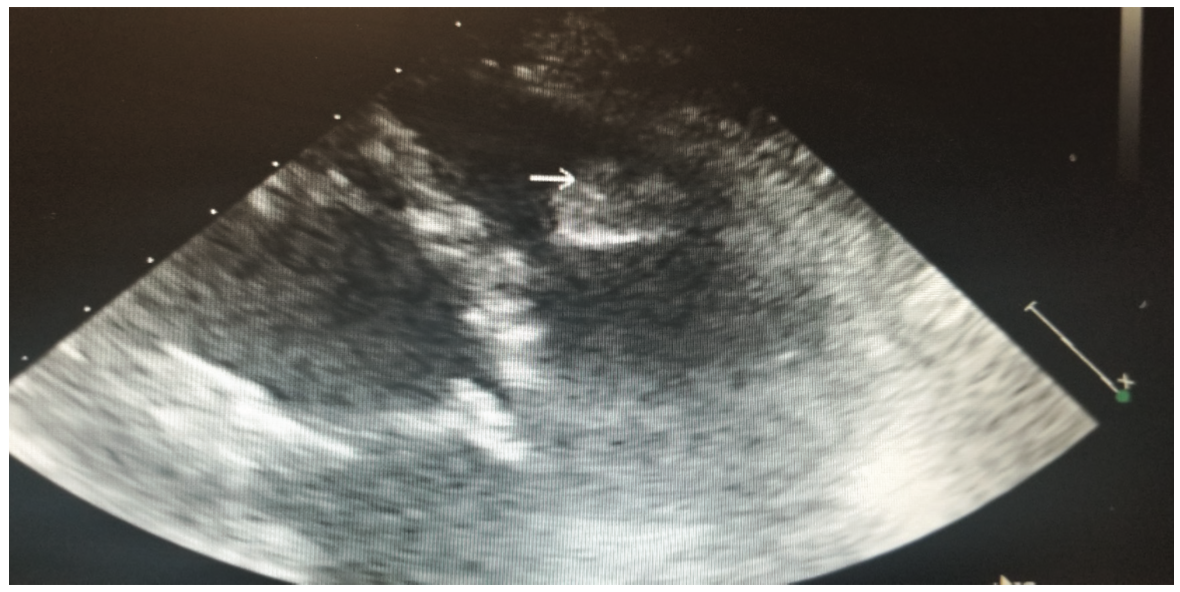

This is a 58-year-old female with a history of tuberous sclerosis. Transthoracic echocardiogram images demonstrated a heterogeneous mass in the mid right ventricle attached to the septum and the moderator band (Figures 1-6). The mass looked similar to what was seen on a transthoracic echocardiogram from a year prior.

The patient had a history of tuberous sclerosis with a solitary left kidney and known renal angiomyolipoma. She had innumerable angiomyolipomas in her left kidney without any normal renal parenchyma. She had undergone right nephrectomy for renal hemorrhage several years ago. She had no known previous history of cardiac disease and no symptoms attributed to the cardiac tumor noted on the echocardiogram. There were no features suggesting the cardiac mass was causing any obstructive pathology.

One of the major differentials for this mass was thought to be cardiac rhabdomyoma, given the patient’s history of tuberous sclerosis with known renal angiomyolipomas. Cardiac rhabdomyomas are usually associated with tuberous sclerosis complex, which is a genetic disorder characterized by hamartomas in multiple organs. Rhabdomyomas may develop at any location in the heart, but the most common locations are ventricular and septal walls.